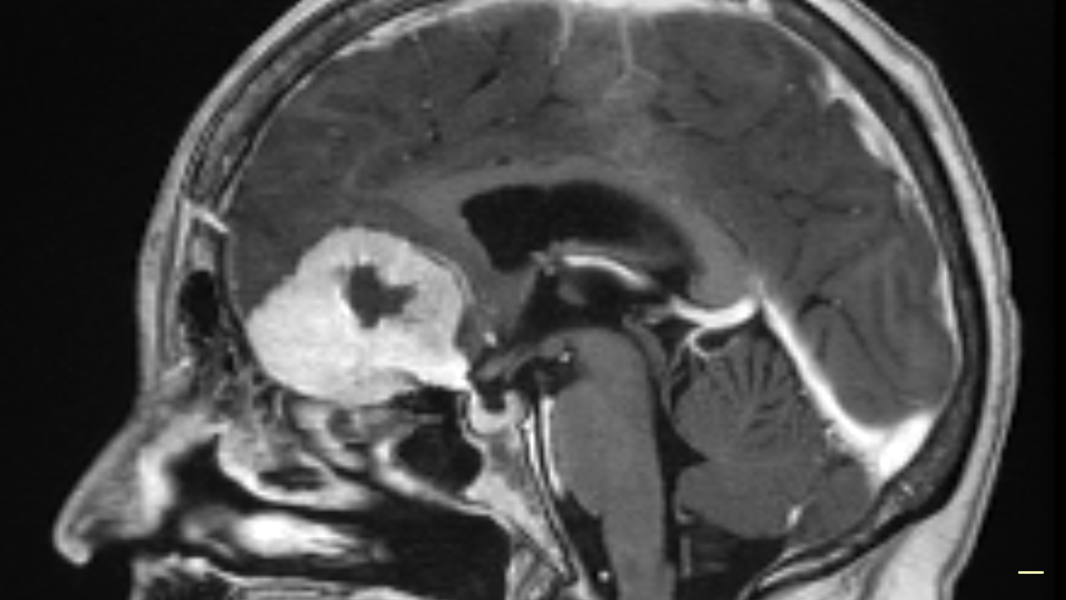

Doreen Adams unterzog sich dem neuen Verfahren im vergangenen Jahr und hat nur Positives zu berichten. Der 75-Jährigen wurde ein "tennisballgroßer" Gehirntumor entfernt. Etwas, das in einer früheren Kraniotomie nicht gelang. Die Seniorin habe nach dem neumethodischen Eingriff kaum die üblichen Nachwirkungen einer Operation gespürt. "Nach der Operation ging es mir großartig", sagte sie. "Ich hatte ein blaues Auge und es dauerte eine Weile, bis es sich öffnete, aber das war alles."

Doreen Adams' Tumor vor der Entfernung.

NHS Grampian